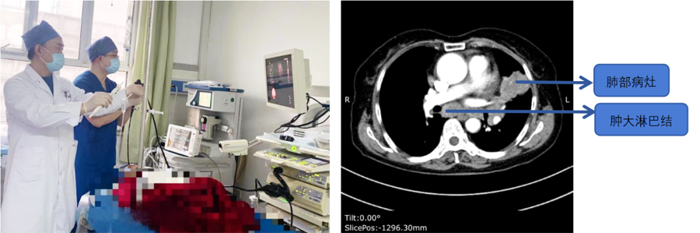

病例1

患者,女,72歲,2月來“反復咳嗽、咳痰,偶咳白痰中帶血絲”,胸部CT提示“肺占位、肺炎”,收住院。完善胸部強化CT提示“左肺占位、肺炎、縱膈多發(fā)淋巴結腫大”,電子支氣管鏡檢查見左肺上葉支氣管血塊及壞死物阻塞,清除后見管腔通暢,刷檢DNA細胞學示“細胞退變明顯,建議進一步檢查”。10月27日行CT引導下肺穿刺活檢,病理示“機化性肺炎”,給予抗感染及激素治療,患者癥狀好轉出院。半月前,患者復查肺CT發(fā)現(xiàn)病灶較前稍有增大,張強主任考慮患者癥狀雖有好轉,但仍存在腫瘤性病變可能性。經(jīng)過討論及與患者家屬充分溝通后,決定實施支氣管內超聲引導下針吸活檢術(EBUS-TBNA)+電子支氣管鏡檢查+現(xiàn)場快速評價(ROSE)技術,以提高診斷陽性率。術中ROSE提示查找到可疑癌細胞,取材量較足分。最后病理檢查明確診斷為低分化肺腺癌,隨后進行基因檢測,明確了治療方向。